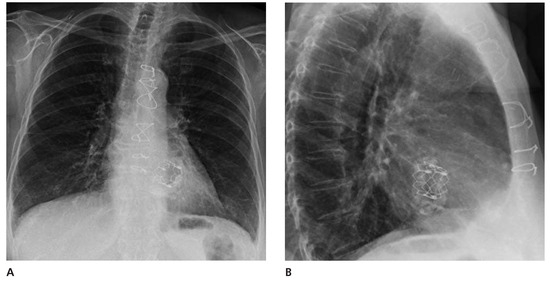

We report on the worldwide first implantation of a transcatheter valve in mitral position using a surgical approach to treat severe combined mitral valve disease, complicated by massive calcifications of the whole mitral anulus. The management of suc...